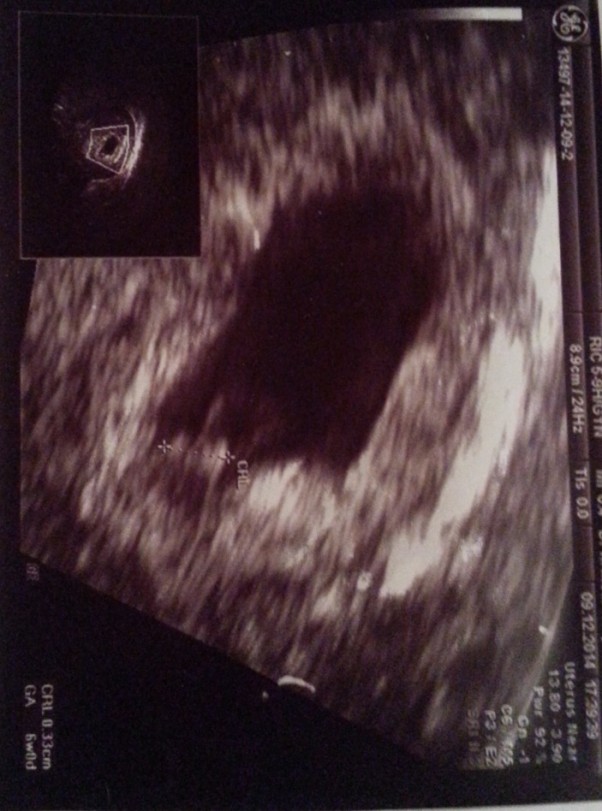

Pierwsza wizyta u lekarza i pierwsze usg. już widać nasze maleństwo a serducho jak dzwon :)